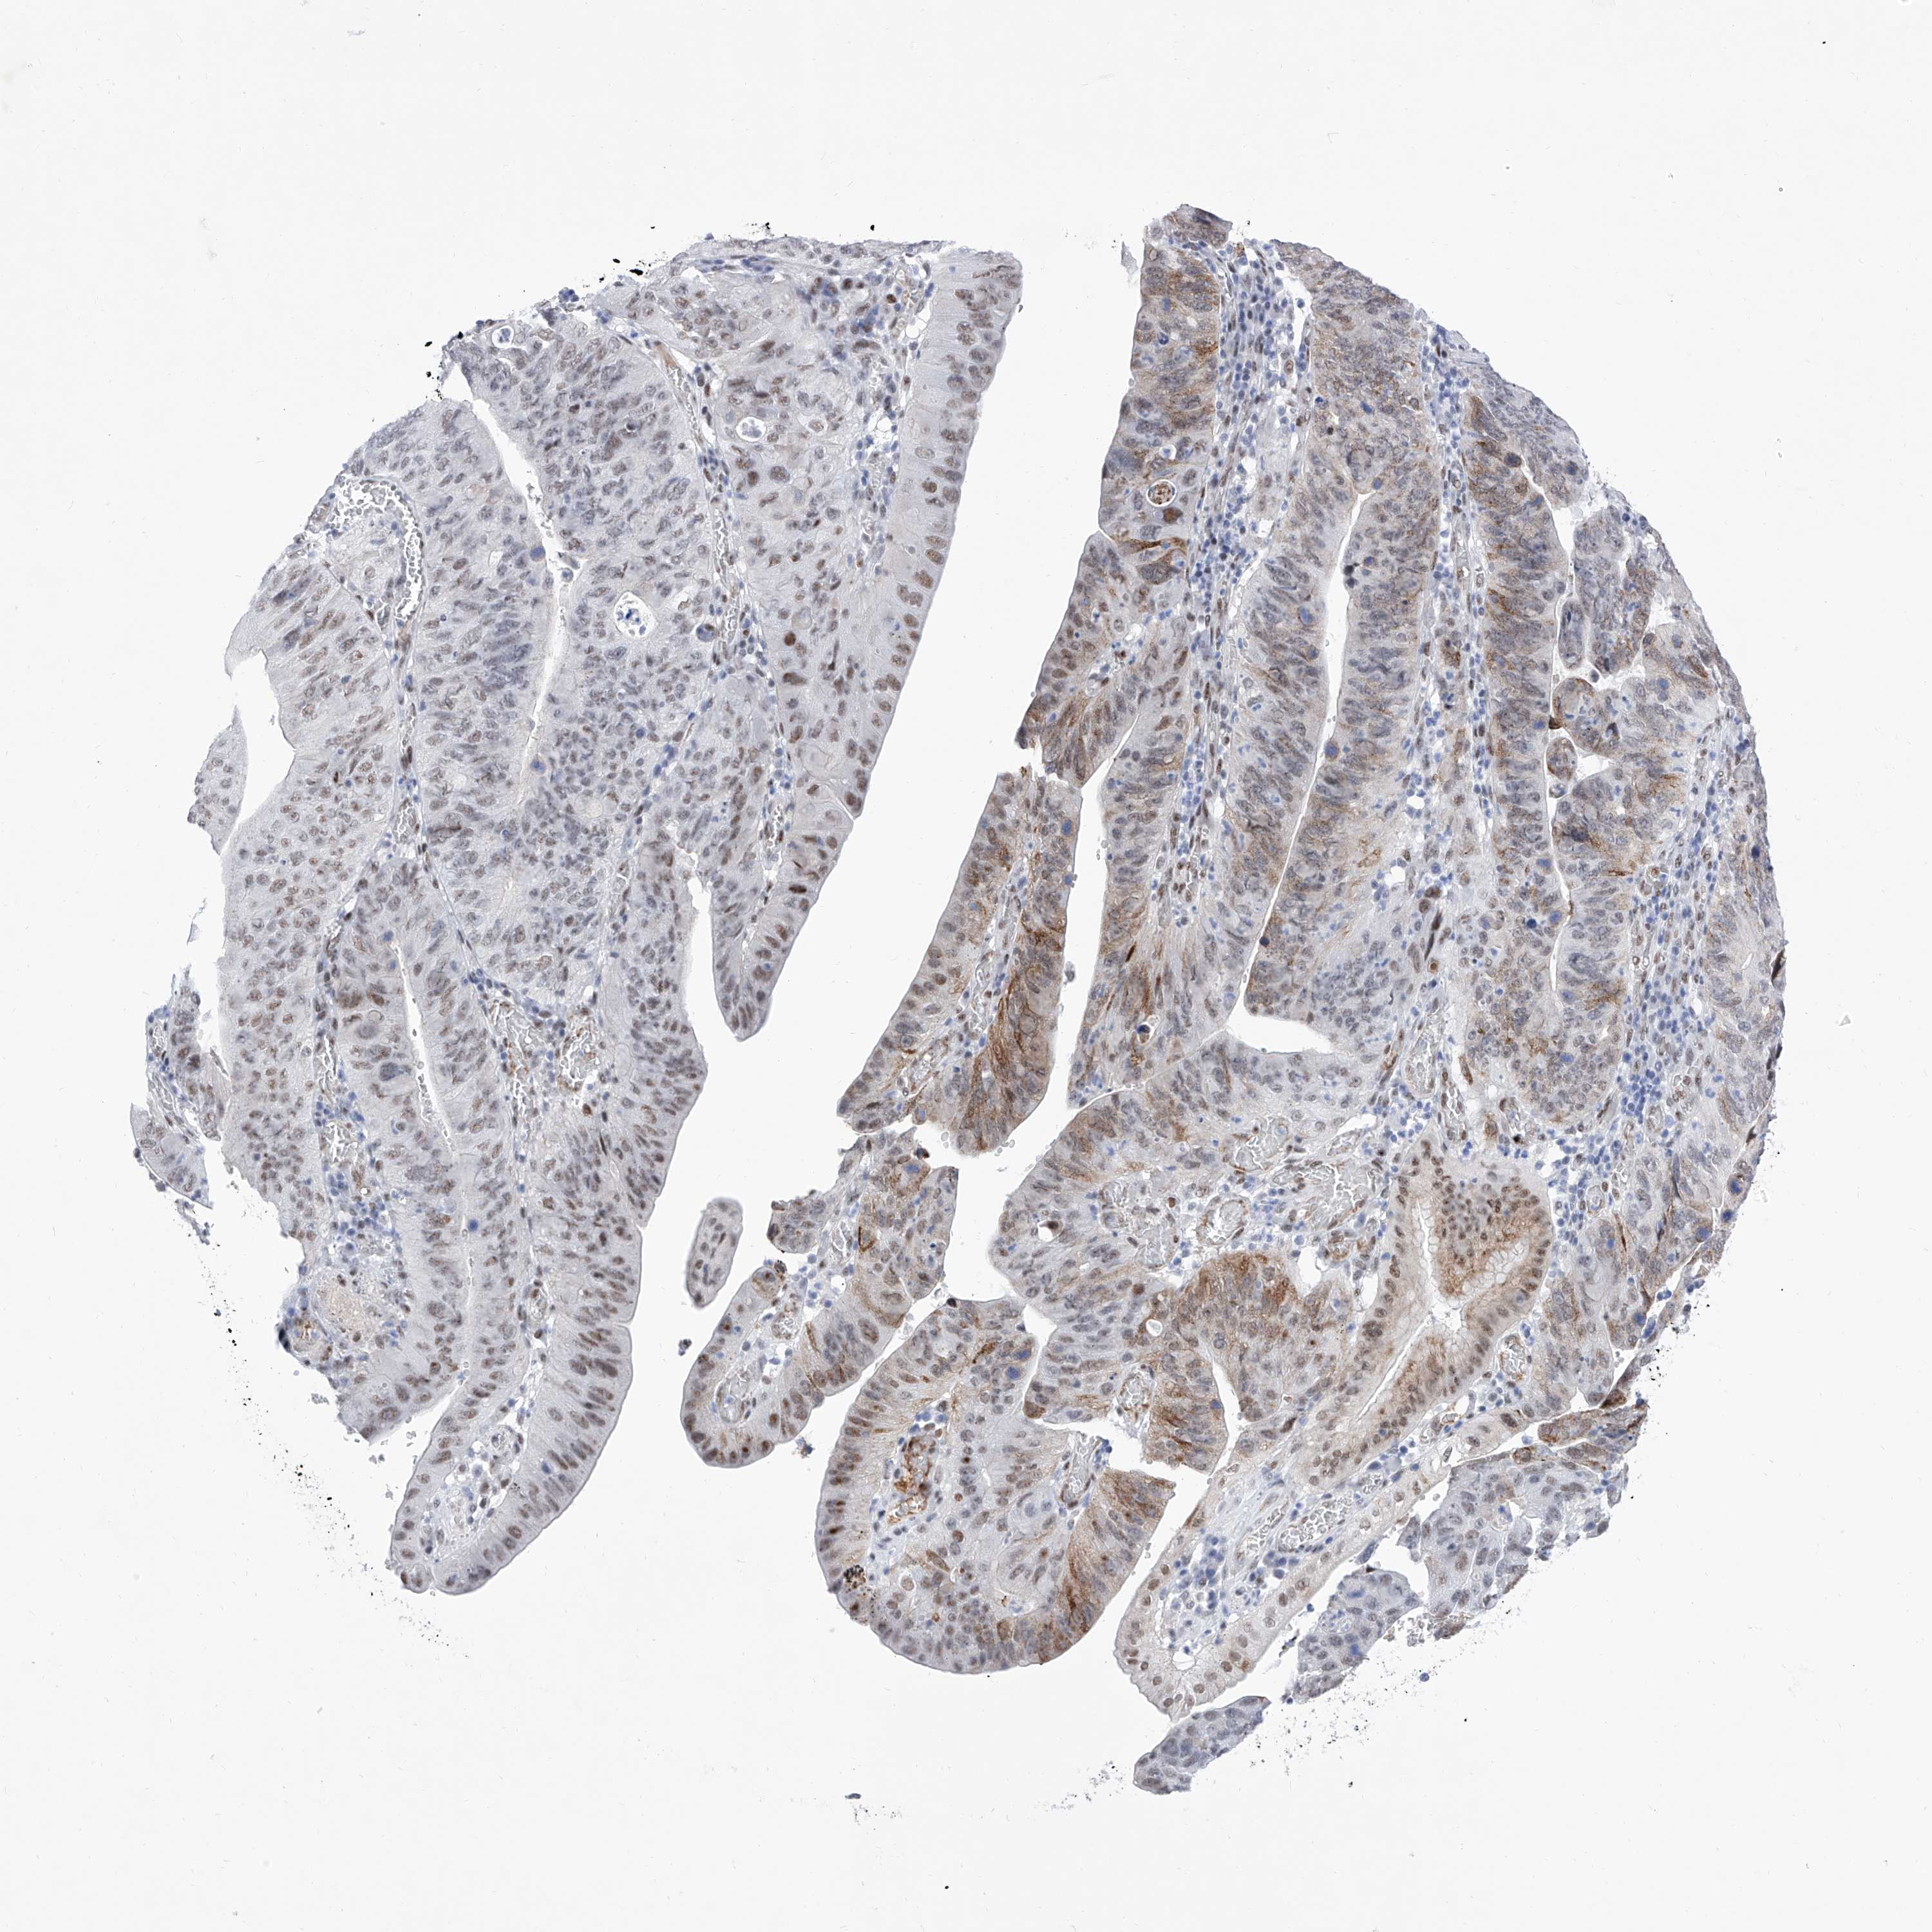

STOMACH CANCER - Protein expressioni

A mouse-over function shows sample information and annotation data. Click on an image to view it in a full screen mode. Samples can be filtered based on level of antibody staining by selecting one or several of the following categories: high, medium, low and not detected. The assay and annotation is described here.

Note that samples used for immunohistochemistry by the Human Protein Atlas do not correspond to samples in the TCGA dataset.

Antibody stainingi

Antibody staining in the annotated cell types in the current human tissue is reported as not detected, low, medium, or high, based on conventional immunohistochemistry profiling in selected tissues. This score is based on the combination of the staining intensity and fraction of stained cells.

Each image is clickable and will lead to virtual microscopy that enables deeper exploration of all samples and also displays staining intensity scores, fraction scores and subcellular localization as well as patient and tissue information for each sample.

Antibody HPA031619

Staining

High

Medium

Low

Not detected

Intensity

Strong

Moderate

Weak

Negative

Quantity

>75%

75%-25%

<25%

None

Location

Nuclear

Cytoplasmic/membranous

Cytoplasmic/membranous,nuclear

Adenocarcinoma, NOS